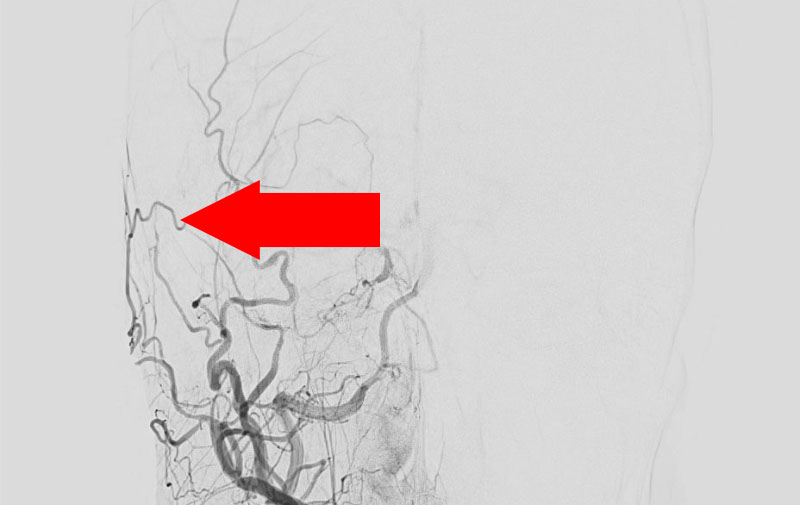

右側頭部硬膜動静脈瘻

手術写真

治療

前

中

後